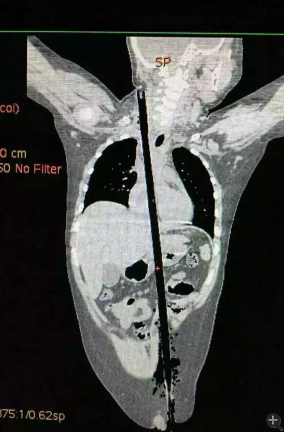

據(jù)相關(guān)知情人介紹,受傷男童24日晚在家中與小朋友一塊兒在墻頭上玩耍時(shí),一不小心從高墻上跌落到了鄰家花圃中,讓人觸目驚心的是,該男童正好跌到了花圃中的一支長約63厘米,直徑約1.5厘米的竹棍上,竹棍自孩子的左側(cè)大腿根部直接插入腹腔并入胸腔直至右側(cè)頸部。

市兒童醫(yī)院組織專家團(tuán)隊(duì)對(duì)孩子的病情進(jìn)行檢查、評(píng)估后發(fā)現(xiàn),竹棍由患兒左側(cè)大腿根部插入,經(jīng)腹腔穿透胃、肝臟、膈肌入胸腔,并穿透患兒心臟,經(jīng)胸腔入頸部,此刻不能拔除竹棍,因?yàn)槿コ窆鲿?huì)導(dǎo)致心臟、肝臟破裂大出血導(dǎo)致休克,危及性命。

由于竹棍自心臟的右心房膈面穿入心臟,并由右房近左房頂處穿出心臟,經(jīng)右胸頂刺入右頸部,右心房破口處緊鄰右冠狀動(dòng)脈,幸運(yùn)的是胸腔內(nèi)大血管無損傷,在體外循環(huán)輔助下,醫(yī)護(hù)團(tuán)隊(duì)異物穿出處鋸斷異物,將插入心臟內(nèi)的竹棍截?cái)喟纬扪a(bǔ)心臟破損處,向上繼續(xù)尋找周圍組織的游離異物,見異物緊臨頸部大血管,經(jīng)精細(xì)手術(shù),終于抽出了異物。整個(gè)手術(shù)時(shí)間花了十多個(gè)小時(shí)。